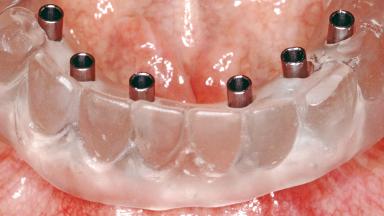

Conventional Loading of Six Implants in the Mandible and Final Restoration with a Full-Arch Metal-Ceramic FDP

A 68-year-old, completely edentulous male patient presented for evaluation and treatment options. He reported excellent general health and was taking no regular medication. He had been edentulous for approximately 12 years, having lost his teeth to periodontal disease and dental caries. The patient’s chief complaint was incompetent function. His secondary concerns included his appearance and the desire for a predictable outcome. He attributed his reduced functional capacity to his lower complete denture, which he described as poor. He was particularly concerned with the denture’s instability and poor fit. In general terms, he was satisfied with the maxillary complete prosthesis. The maxillary prosthesis was characterized by adequate retention, stability, and support, although the fit was considered less than ideal.

# of Implants 6

Type of Implants One-Piece